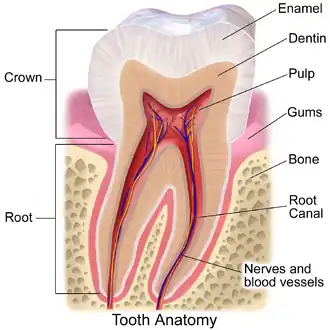

Tooth enamel is one of the four major tissues that make up the tooth in humans and many animals, including some species of fish. It makes up the normally visible part of the tooth, covering the crown. The other major tissues are dentin, cementum, and dental pulp. It is a very hard, white to off-white, highly mineralised substance that acts as a barrier to protect the tooth but can become susceptible to degradation, especially by acids from food and drink. In rare circumstances enamel fails to form, leaving the underlying dentin exposed on the surface.[1]

Enamel is the hardest substance in the human body and contains the highest percentage of minerals (at 96%),[2] with water and organic material composing the rest.[3] The primary mineral is hydroxyapatite, which is a crystalline calcium phosphate.[4] Enamel is formed on the tooth while the tooth develops within the jaw bone before it erupts into the mouth. Once fully formed, enamel does not contain blood vessels or nerves, and is not made of cells. Remineralisation of teeth can repair damage to the tooth to a certain degree but damage beyond that cannot be repaired by the body. The maintenance and repair of human tooth enamel is one of the primary concerns of dentistry.

In humans, enamel varies in thickness over the surface of the tooth, often thickest at the cusp, up to 2.5 mm, and thinnest at its border with the cementum at the cementoenamel junction (CEJ).[5]

The large amount of mineral in enamel accounts not only for its strength but also for its brittleness.[6] Tooth enamel ranks 5 on Mohs hardness scale (between steel and titanium) and has a Young's modulus of 83 GPa.[4] Dentin, less mineralized and less brittle, 3–4 in hardness, compensates for enamel and is necessary as a support.[7] On radiographs, the differences in the mineralization of different portions of the tooth and surrounding periodontium can be noted; enamel appears lighter than dentin or pulp since it is denser than both and more radiopaque.[8]